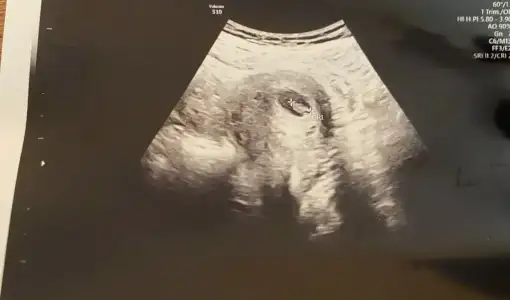

Bende yeniyim öncelikle☺️Mesajlarınızı dikkatle okudum bana da doktorum kesin birşey demedi 13.haftadayım yorumlar Mısınız acaba